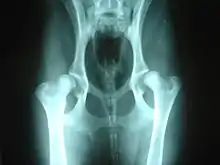

La gravedad de la displasia se puede medir si trazamos el denominado ángulo de Norberg. Éste consiste en trazar sobre una radiografía una línea que vaya desde el centro de una cabeza del fémur, al centro de la otra. Posteriormente, desde ambos extremos se traza otra línea que pase por el borde acetabular dorsal, formando así un ángulo con la anterior. Según la amplitud del ángulo, tenemos que:

- No se presenta displasia si es mayor de 105.º.

- Si mide entre 100°-105.º, el animal tiene displasia leve.

- Si mide entre 90°-100º, la displasia es moderada. Se acompaña de enfermedad degenerativa articular y aplanamiento del acetábulo.

- Si mide menos de 90°, la displasia es grave. Puede llegar a presentar luxación.